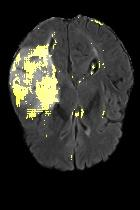

Current unsupervised anomaly localization approaches rely on generative models to learn the distribution of normal images, which is later used to identify potential anomalous regions derived from errors on the reconstructed images. However, a main limitation of nearly all prior literature is the need of employing anomalous images to set a class-specific threshold to locate the anomalies. This limits their usability in realistic scenarios, where only normal data is typically accessible. Despite this major drawback, only a handful of works have addressed this limitation, by integrating supervision on attention maps during training. In this work, we propose a novel formulation that does not require accessing images with abnormalities to define the threshold. Furthermore, and in contrast to very recent work, the proposed constraint is formulated in a more principled manner, leveraging well-known knowledge in constrained optimization. In particular, the equality constraint on the attention maps in prior work is replaced by an inequality constraint, which allows more flexibility. In addition, to address the limitations of penalty-based functions we employ an extension of the popular log-barrier methods to handle the constraint. Comprehensive experiments on the popular BRATS'19 dataset demonstrate that the proposed approach substantially outperforms relevant literature, establishing new state-of-the-art results for unsupervised lesion segmentation.

翻译:目前未受监督的异常本地化方法依靠基因模型来了解正常图像的分布,这些模型后来被用于确定从重建图像错误中得出的潜在异常区域。然而,几乎所有先前文献的主要局限性是,需要使用异常图像来设定一个特定等级的阈值以定位异常。这限制了其在现实情景中的可用性,在现实情景中,只有通常能获取正常数据。尽管存在这一重大缺陷,但只有少数作品通过在培训中整合对关注地图的监督,解决了这一局限性。在这项工作中,我们提议了一种新颖的提法,不要求使用异常图像来界定阈值。此外,与最近的工作相反,拟议的限制是以更加有原则的方式拟订的,在限制优化时利用众所周知的知识。特别是,先前工作中对关注地图的平等性制约被一种不平等性制约所取代,这允许更大的灵活性。此外,为了解决基于惩罚的功能的局限性,我们采用了流行的日志障碍方法来应对这一制约。我们建议对流行的BRATS'19数据设置进行综合实验,这与最近的工作不同,因此,拟议的限制是以更加有原则的方式提出了限制,即拟议的方法大大地超越了相关的分段结果。